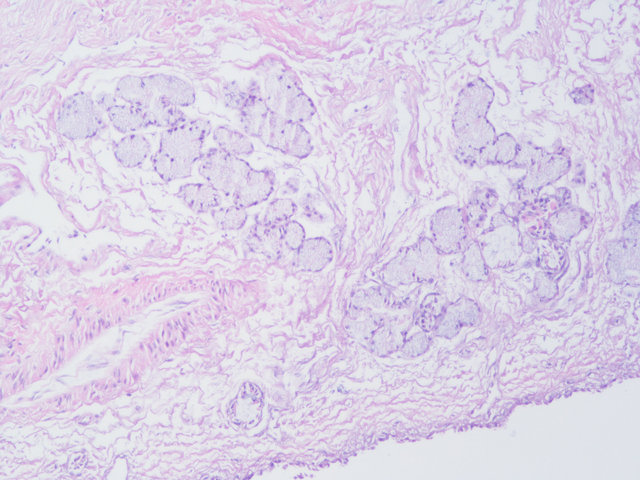

样片参考:

肠

鼻粘膜